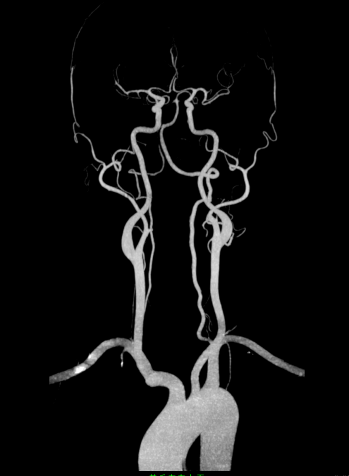

Chẩn đoán hình ảnh mô mềm tiên tiến cho vùng bụng.

Tăng cường độ tương phản I-ốt.

Hỗ trợ đánh giá an toàn cho bệnh nhân.

Đảm bảo hình ảnh chất lượng cao.